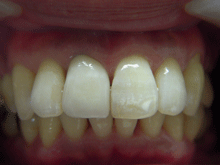

ハイブリッドセラミックス

ハイブリッドセラミックスとはセラミック粒子を92%含有した白い材料で、セラミックスのもつ審美性と耐久性、

より天然歯に近い硬さの材料です。

症 例